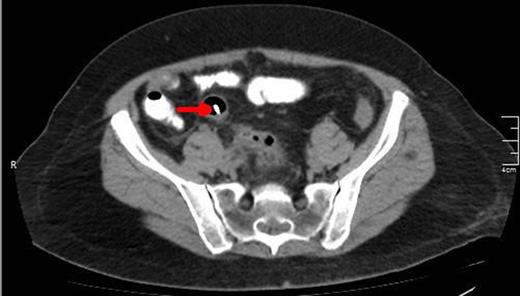

A CT view of the same patient showing the lower edge of the biliary stent perforating the sigmoid colon (red arrow).